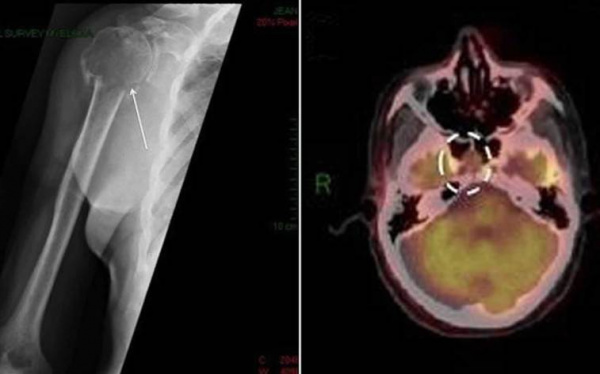

(а) Пациент с жалобами на боли в груди. При МРТ на Т2ВИ FS в правых отделах грудной стенки определяется крупное гиперинтенсивное объемное образование с дольчатым контуром.

(б) У этого же пациента при МРТ на Т1ВИ FS с контрастным усилением наблюдается повышение интенсивности сигнала от образования.

При биопсии была выявлена солитарная плазмоцитома. Данные признаки типичны для образования при выполнении МРТ до начала лечения.